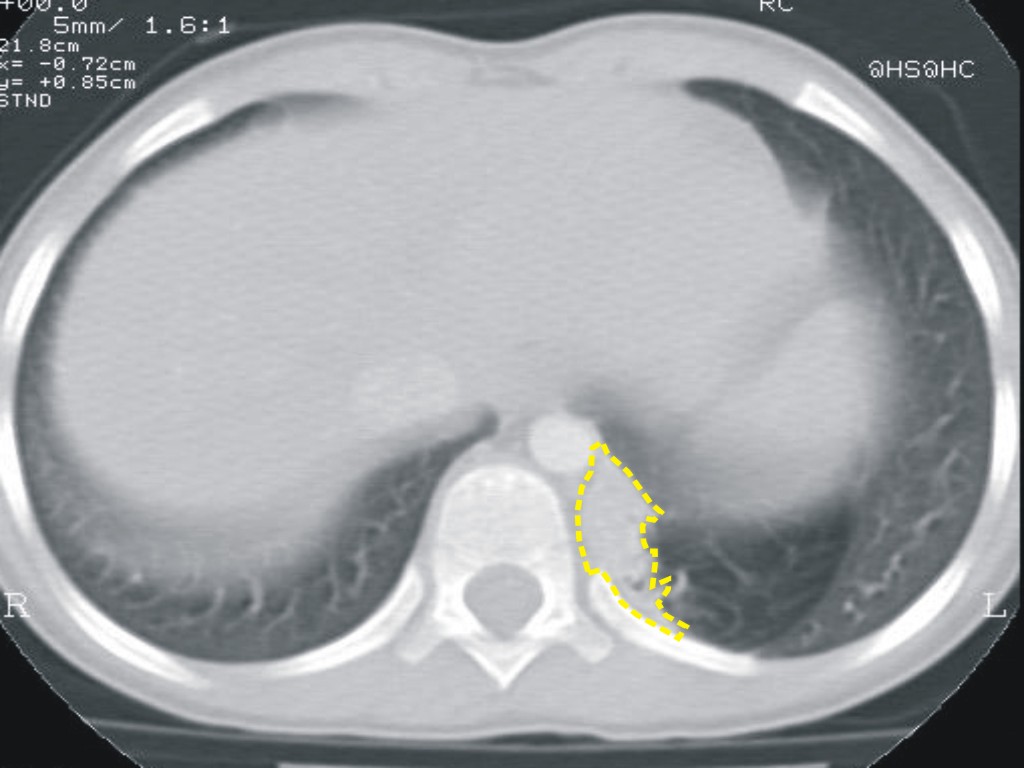

R. � una bambina di 4 anni in cui la diagnosi di malformazione polmonare era stata posta all�et� di 3 anni, come reperto tardivo, secondario a episodi broncopneumonici basali a sinistra. In tale occasione era stata evidenziata per la prima volta lesione microcistica basale sinistra associata ad area enfisematosa perilesionale (Figura 4).

Figura 4 |